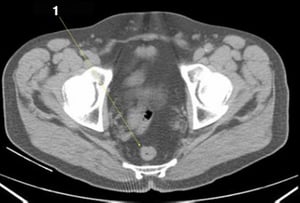

CT-Scan von Abdomen und Becken mit normaler Anatomie ohne Kontrastmittel (Folie 25)

1 = Colon sigmoideum.

© Springer Science+Business Media